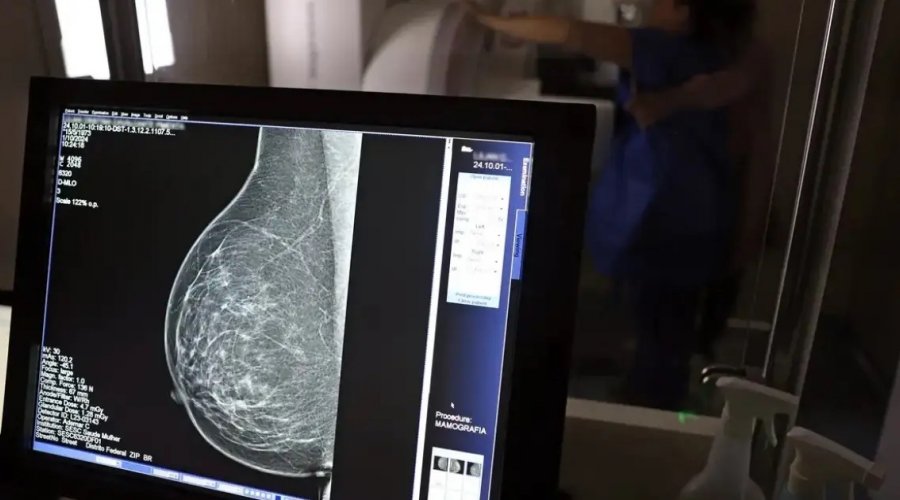

O presidente Luiz Inácio Lula da Silva sancionou a Lei nº 15.284, que amplia o acesso das mulheres ao exame de mamografia pelo Sistema Único de Saúde (SUS). Publicada nesta sexta-feira (19) no Diário Oficial da União, a nova norma assegura o direito ao exame para todas as mulheres a partir dos 40 anos, seguindo diretrizes do Ministério da Saúde.

A legislação modifica a Lei nº 11.664, de 2008, que trata das ações de prevenção, diagnóstico e tratamento dos cânceres de mama, colo do útero e colorretal no âmbito do SUS. Com a atualização, o exame passa a ser garantido mesmo para mulheres que não apresentem sintomas ou histórico familiar da doença, ampliando o alcance do rastreamento precoce.

Dados do Ministério da Saúde apontam que a faixa etária entre 40 e 49 anos concentra cerca de 23% dos casos de câncer de mama. A detecção antecipada aumenta significativamente as chances de cura e reduz a necessidade de tratamentos mais agressivos.

Segundo o ministro da Saúde, Alexandre Padilha, a medida representa um avanço histórico na política de atenção à saúde da mulher. O SUS realizou, somente em 2024, cerca de 4 milhões de mamografias de rastreamento e mais de 376 mil exames diagnósticos, reforçando a importância da prevenção como estratégia de cuidado e de salvamento de vidas.